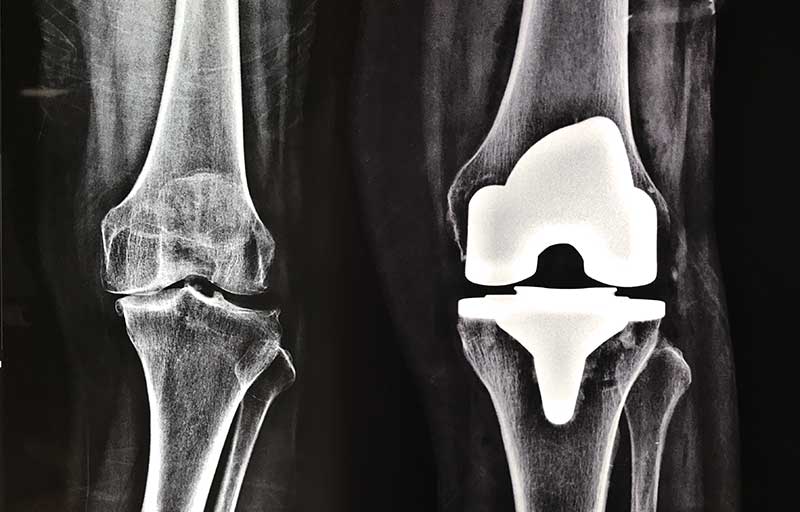

• Operasi penggantian sendi lutut adalah operasi yang dilakukan untuk mengganti sendi lutut yang telah mengalami kerusakan akibat pengapuran sendi dengan sendi lutut buatan. Pengapuran sendi paling sering mengenai sendi lutut sehingga operasi penggantian sendi lutut merupakan operasi penggantian sendi yang paling banyak dilakukan.

Operasi penggantian sendi lutut bermanfaat menghilangkan nyeri sendi akibat pengapuran sendi dan memperbaiki bentuk lutut yang bengkok menjadi lurus kembali.